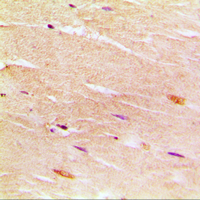

Immunohistochemical analysis of SERCA1 staining in human muscle formalin fixed paraffin embedded tissue section. The section was pre-treated using heat mediated antigen retrieval with sodium citrate buffer (pH 6.0). The section was then incubated with the antibody at room temperature and detected using an HRP conjugated compact polymer system. DAB was used as the chromogen. The section was then counterstained with haematoxylin and mounted with DPX. -